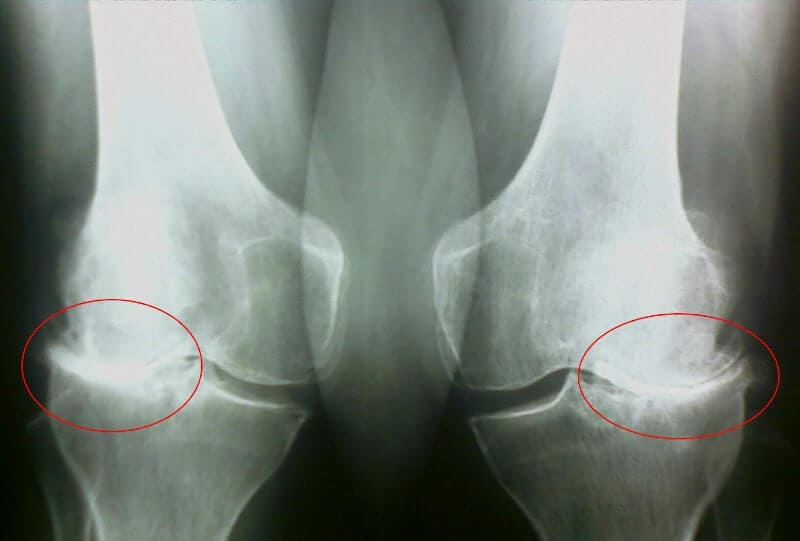

Musiałem iść do lekarza, moja żona nalegała na to. Lekarz rodzinny wysłał mnie do reumatologa, do którego udało mi się dostać w ponad miesiąc, kolejka jednak mocno mnie wymęczyła, w końcu miałem już mocno zniszczone stawy. Przyjął mnie starszy lekarz, bez słowa wysłał na prześwietlenie i badania krwi/moczu. Na drugiej wizycie zdiagnozowano mnie w kilka minut - jakaś artroza, pierwotna czy wtórna, teraz nawet nie pamiętam.

35 dzień: Zrobiłem badania i prześwietlenie. Żadnych śladów artrozy! Chrząstka stawowa jak u 30-letniego faceta. Lekarz powiedział, że na poprzednim RTG najprawdopodobniej był ubytek, więc diagnoza artroza była błędna.